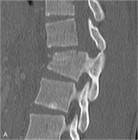

1. CT、MRI:MRIは脊椎と脊髄の同時評価が可能であり有用性が高い。しかし撮像時間を有するならCTを優先させる(推奨度1)